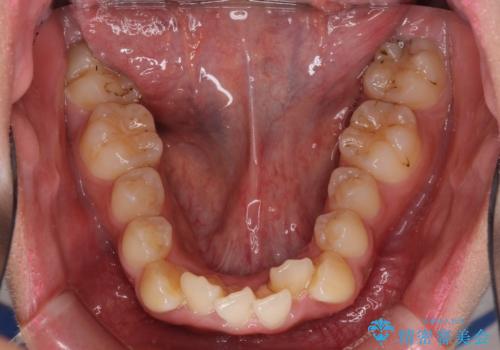

- 八重歯と上下前歯のでこぼこを気にして来院された患者様です。

上下前歯部叢生のスペース獲得のため、上下顎左右小臼歯各1歯(計4本)と全ての親知らずを抜歯して、矯正治療を行うこととしました。

上下の正中位置が大きくずれていたため、治療期間の長期化や正中が合わないまま終了することが予想されましたが、思っていた以上にスムーズに歯が移動し、満足いただける仕上がりとなりました。